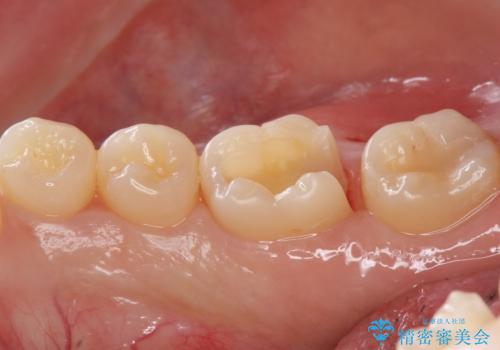

- 右下6 セラミックインレー 77,000円費用は治療当時の料金となります

虫歯が大きくなりきる前に治療を行えたため、歯の削る量を抑えることができました。

精度の良い詰め物は今後の虫歯リスクを抑えることにもつながります。